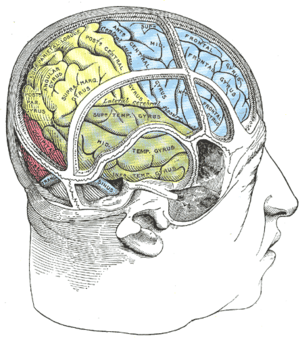

The frontal lobe bottom can be divided into a lateral, polar, orbital (above the orbit; also called basal or ventral), and medial part. Each of these parts consists of particular gyri:

- Lateral part: lateral part of the superior frontal gyrus, middle frontal gyrus, inferior frontal gyrus.

- Polar part: Transverse frontopolar gyri, frontomarginal gyrus.

- Orbital part: Lateral orbital gyrus, anterior orbital gyrus, posterior orbital gyrus, medial orbital gyrus, gyrus rectus.

- Medial part: Medial part of the superior frontal gyrus, cingulate gyrus.

The gyri are separated by sulci. E.g., the precentral gyrus is in front of the central sulcus, and behind the precentral sulcus. The superior and middle frontal gyri are divided by the superior frontal sulcus. The middle and inferior frontal gyri are divided by the inferior frontal sulcus.

Human brain showing the four major lobes of the cerebrum. Beneath the cerebral cortex are the cerebellum, pons, olive, and medulla oblongata Drawing to illustrate the relations of the brain to the skull.

Drawing to illustrate the relations of the brain to the skull.- Frontal lobe